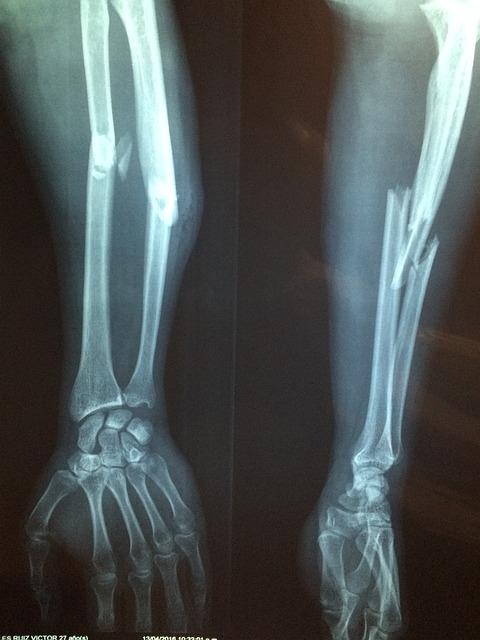

연골은 관절을 보호하는 부드러운 조직으로, 관절의 원활한 움직임을 돕고 충격을 흡수합니다. 연령 증가, 부상, 또는 특정 건강 상태로 인해 연골이 손상되거나 마모될 수 있으며, 콘드로이친은 이러한 연골의 손상을 늦추거나 관절 건강을 개선하는 데 도움을 줄 수 있습니다.

콘드로이친은 본질적으로 긴 사슬의 당류 분자인 글리코사미노글리칸의 일종입니다. 이 구조는 주로 연골 내에서 발견되며, 연골 세포 간의 공간을 채워주고 윤활 및 충격 흡수 기능을 제공합니다.

- 콘드로이친 황산염: 이 형태의 콘드로이친은 연골의 건강을 지원하는 데 사용되며, 황산 그룹이 붙은 긴 사슬 폴리사카라이드 구조를 가집니다. 황산 그룹은 콘드로이친이 수분을 끌어당기고 보유하는 데 도움을 주어, 연골의 탄력성과 충격 흡수 능력을 증진시킵니다.

- 수분 보유 증진: 콘드로이친은 연골 내 수분 보유 능력을 증가시켜 연골이 부드럽고 유연하게 유지되도록 돕습니다. 이는 관절의 움직임을 원활하게 하고 마모를 줄이는 데 중요합니다.

- 연골 보호: 콘드로이친은 연골 세포를 자극하여 핵심 연골 구성 요소인 콜라겐과 프로테오글리칸의 합성을 촉진합니다. 또한, 연골을 분해하는 효소의 활동을 억제하여 연골 손상을 늦출 수 있습니다.